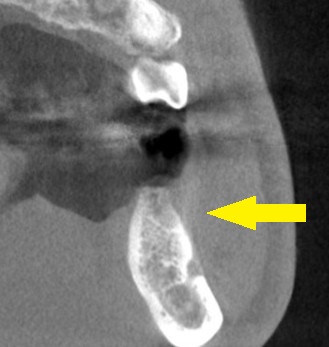

抜歯後5か月でCTを撮影すると、骨はかなり再生されているのですが、骨幅やや不足していました(下の写真下段中)。

そこで、インプラント埋入と同時に、人工骨を補填して、骨幅を増やす手術を併用する計画としました。